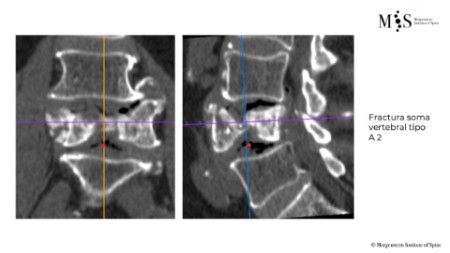

Comparació pre- i post-operatoria d’una cifopastia cementada

Dona, edat 55 anys, fractura aixafament dret de L2

Abans 1

Després 1

Abans 2

Després 2